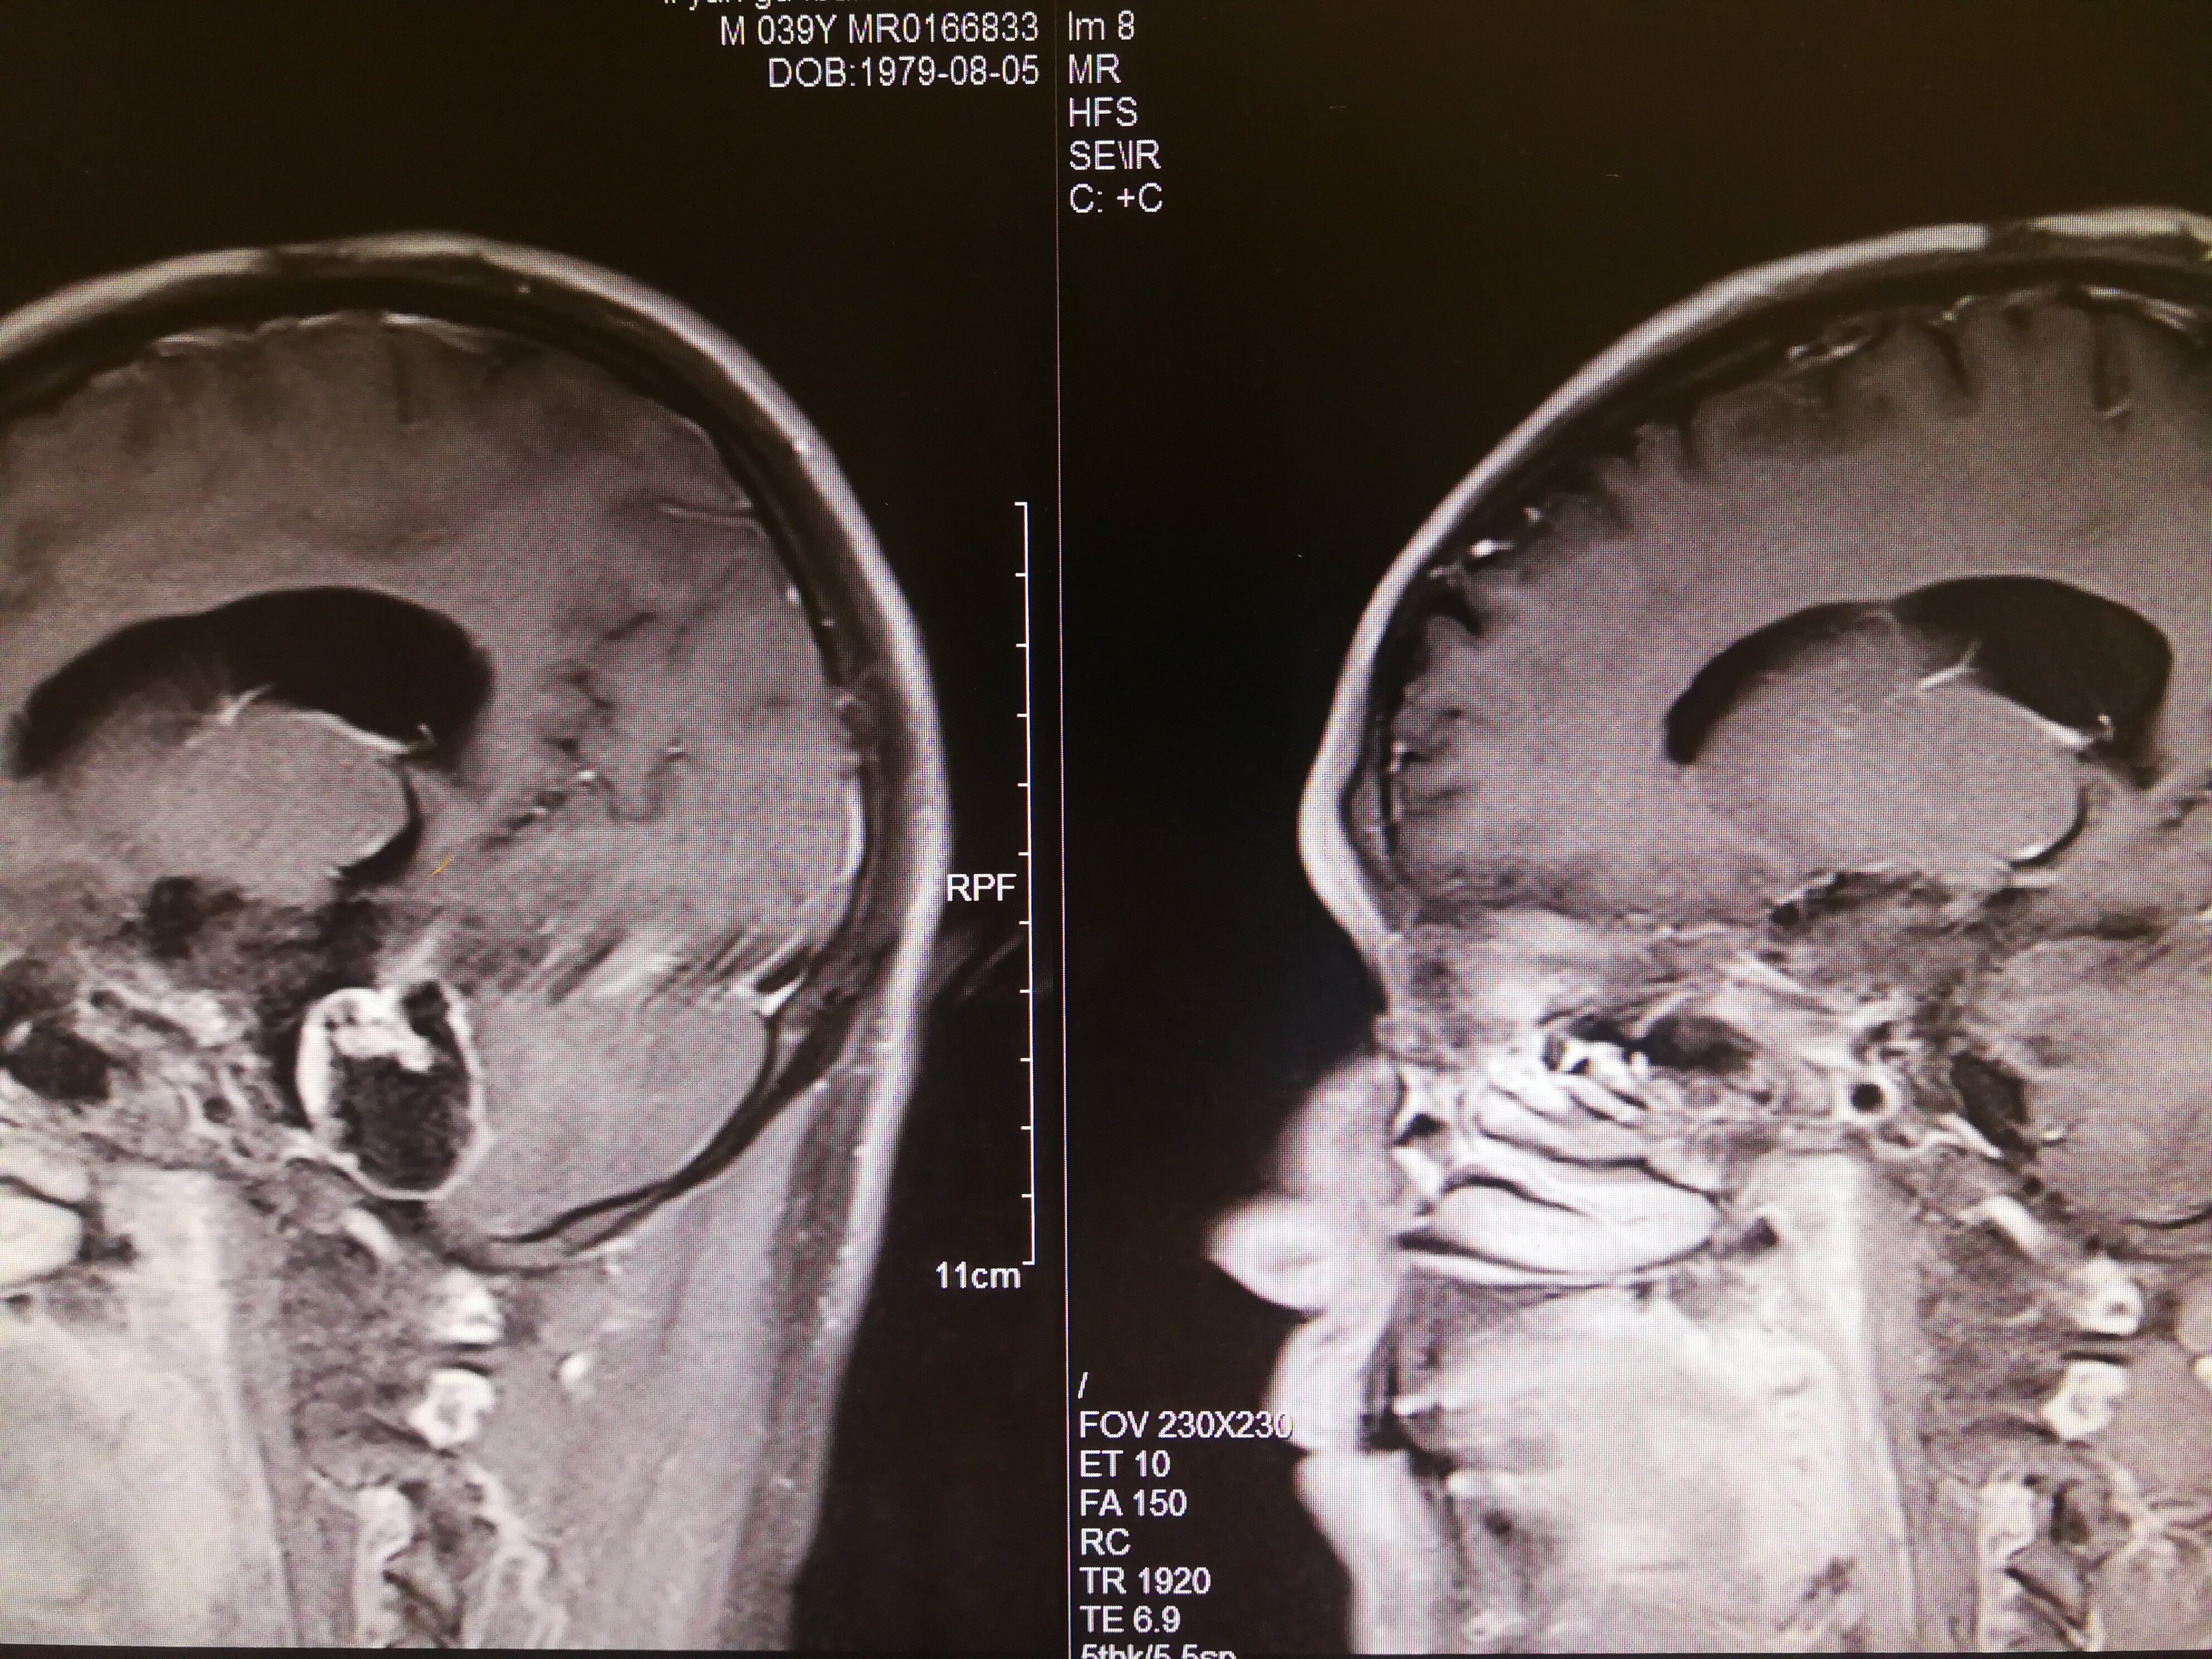

手术治疗听神经瘤是最主要的治疗方式,目前听神经瘤的手术已经非常成熟,只要没有明显的手术禁忌症首先应考虑手术治疗,并要求在电生理监测条件下完成手术,这样可以最大限度地保护面神经功能。以下是几例我们做的听神经鞘瘤手术前后核磁共振片子对照,除手术后听力不能恢复外,没有面瘫,脸部麻木,吞咽困难等颅神经症状,也无其他较明显的手术并发症发生。